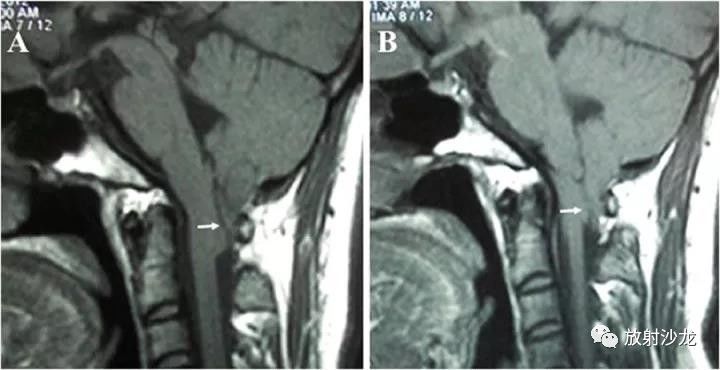

体魄检查中,神经系统检查未见显著异常。影像学检查中,MRI显示出小脑扁桃体下垂至枕骨大孔以下水平,即Chiari畸形1型(见图1)。患者拒绝了脑部手术或常规使用头痛药物,而是通过避免触发因素来管理头痛症状。

图1 矢状位MRI显示小脑扁桃体的尾部下移(箭头)